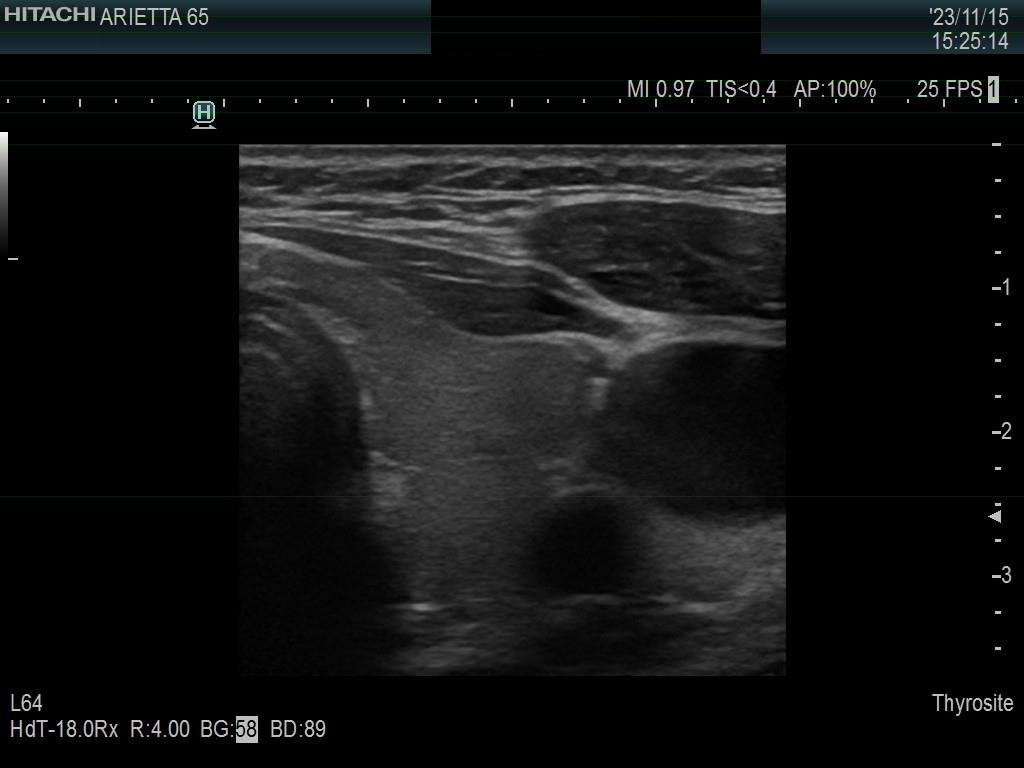

Left lobe, another transverse scan. The ventral and dorsal parts do not differ in their echogenicity.